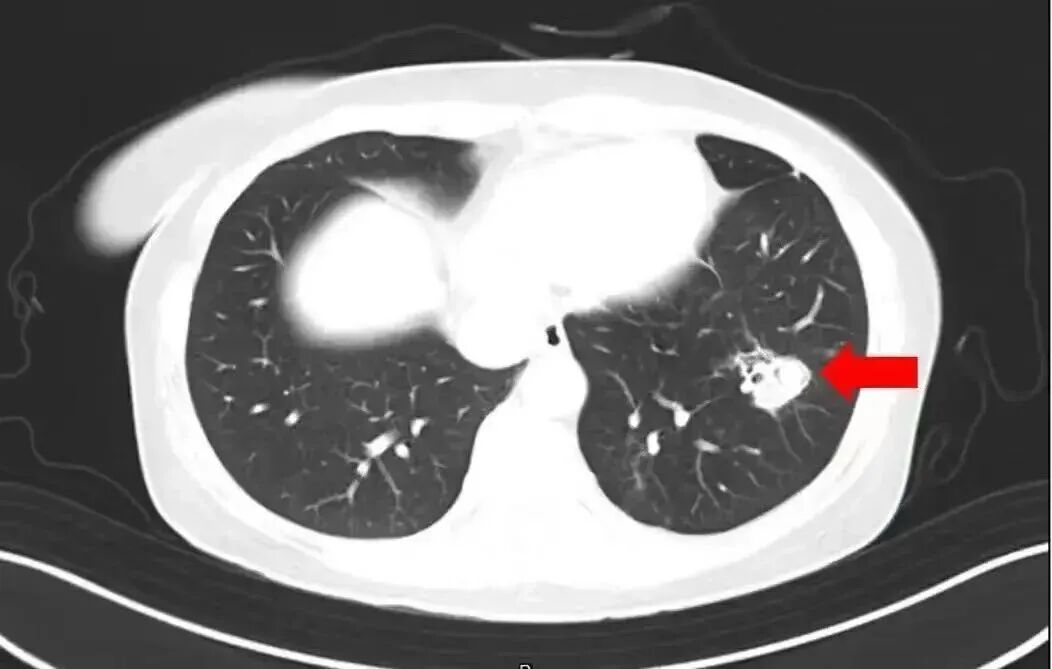

2025年1月,江苏扬州的张大爷为理睬春节启动大扫除,清扫经由中失慎吸入大批灰尘和霉菌孢子,导致哮喘发作。张大爷立时服用了常备的哮喘治愈药物,可症状反而迟缓加剧。经查验,张大爷的肺部出现感染,确诊为肺曲霉病。

北京佑安病院感染概述科主任医师李侗曾先容,关于免疫力低下的东说念主,吸入了这些真菌,就会发病引起肺部的病变——曲霉肺炎。因为它是通过呼吸说念感染的,参加血液后是不错扩散到全身。大脑因为血供最丰富,是以亦然真菌最容易滋扰的器官。